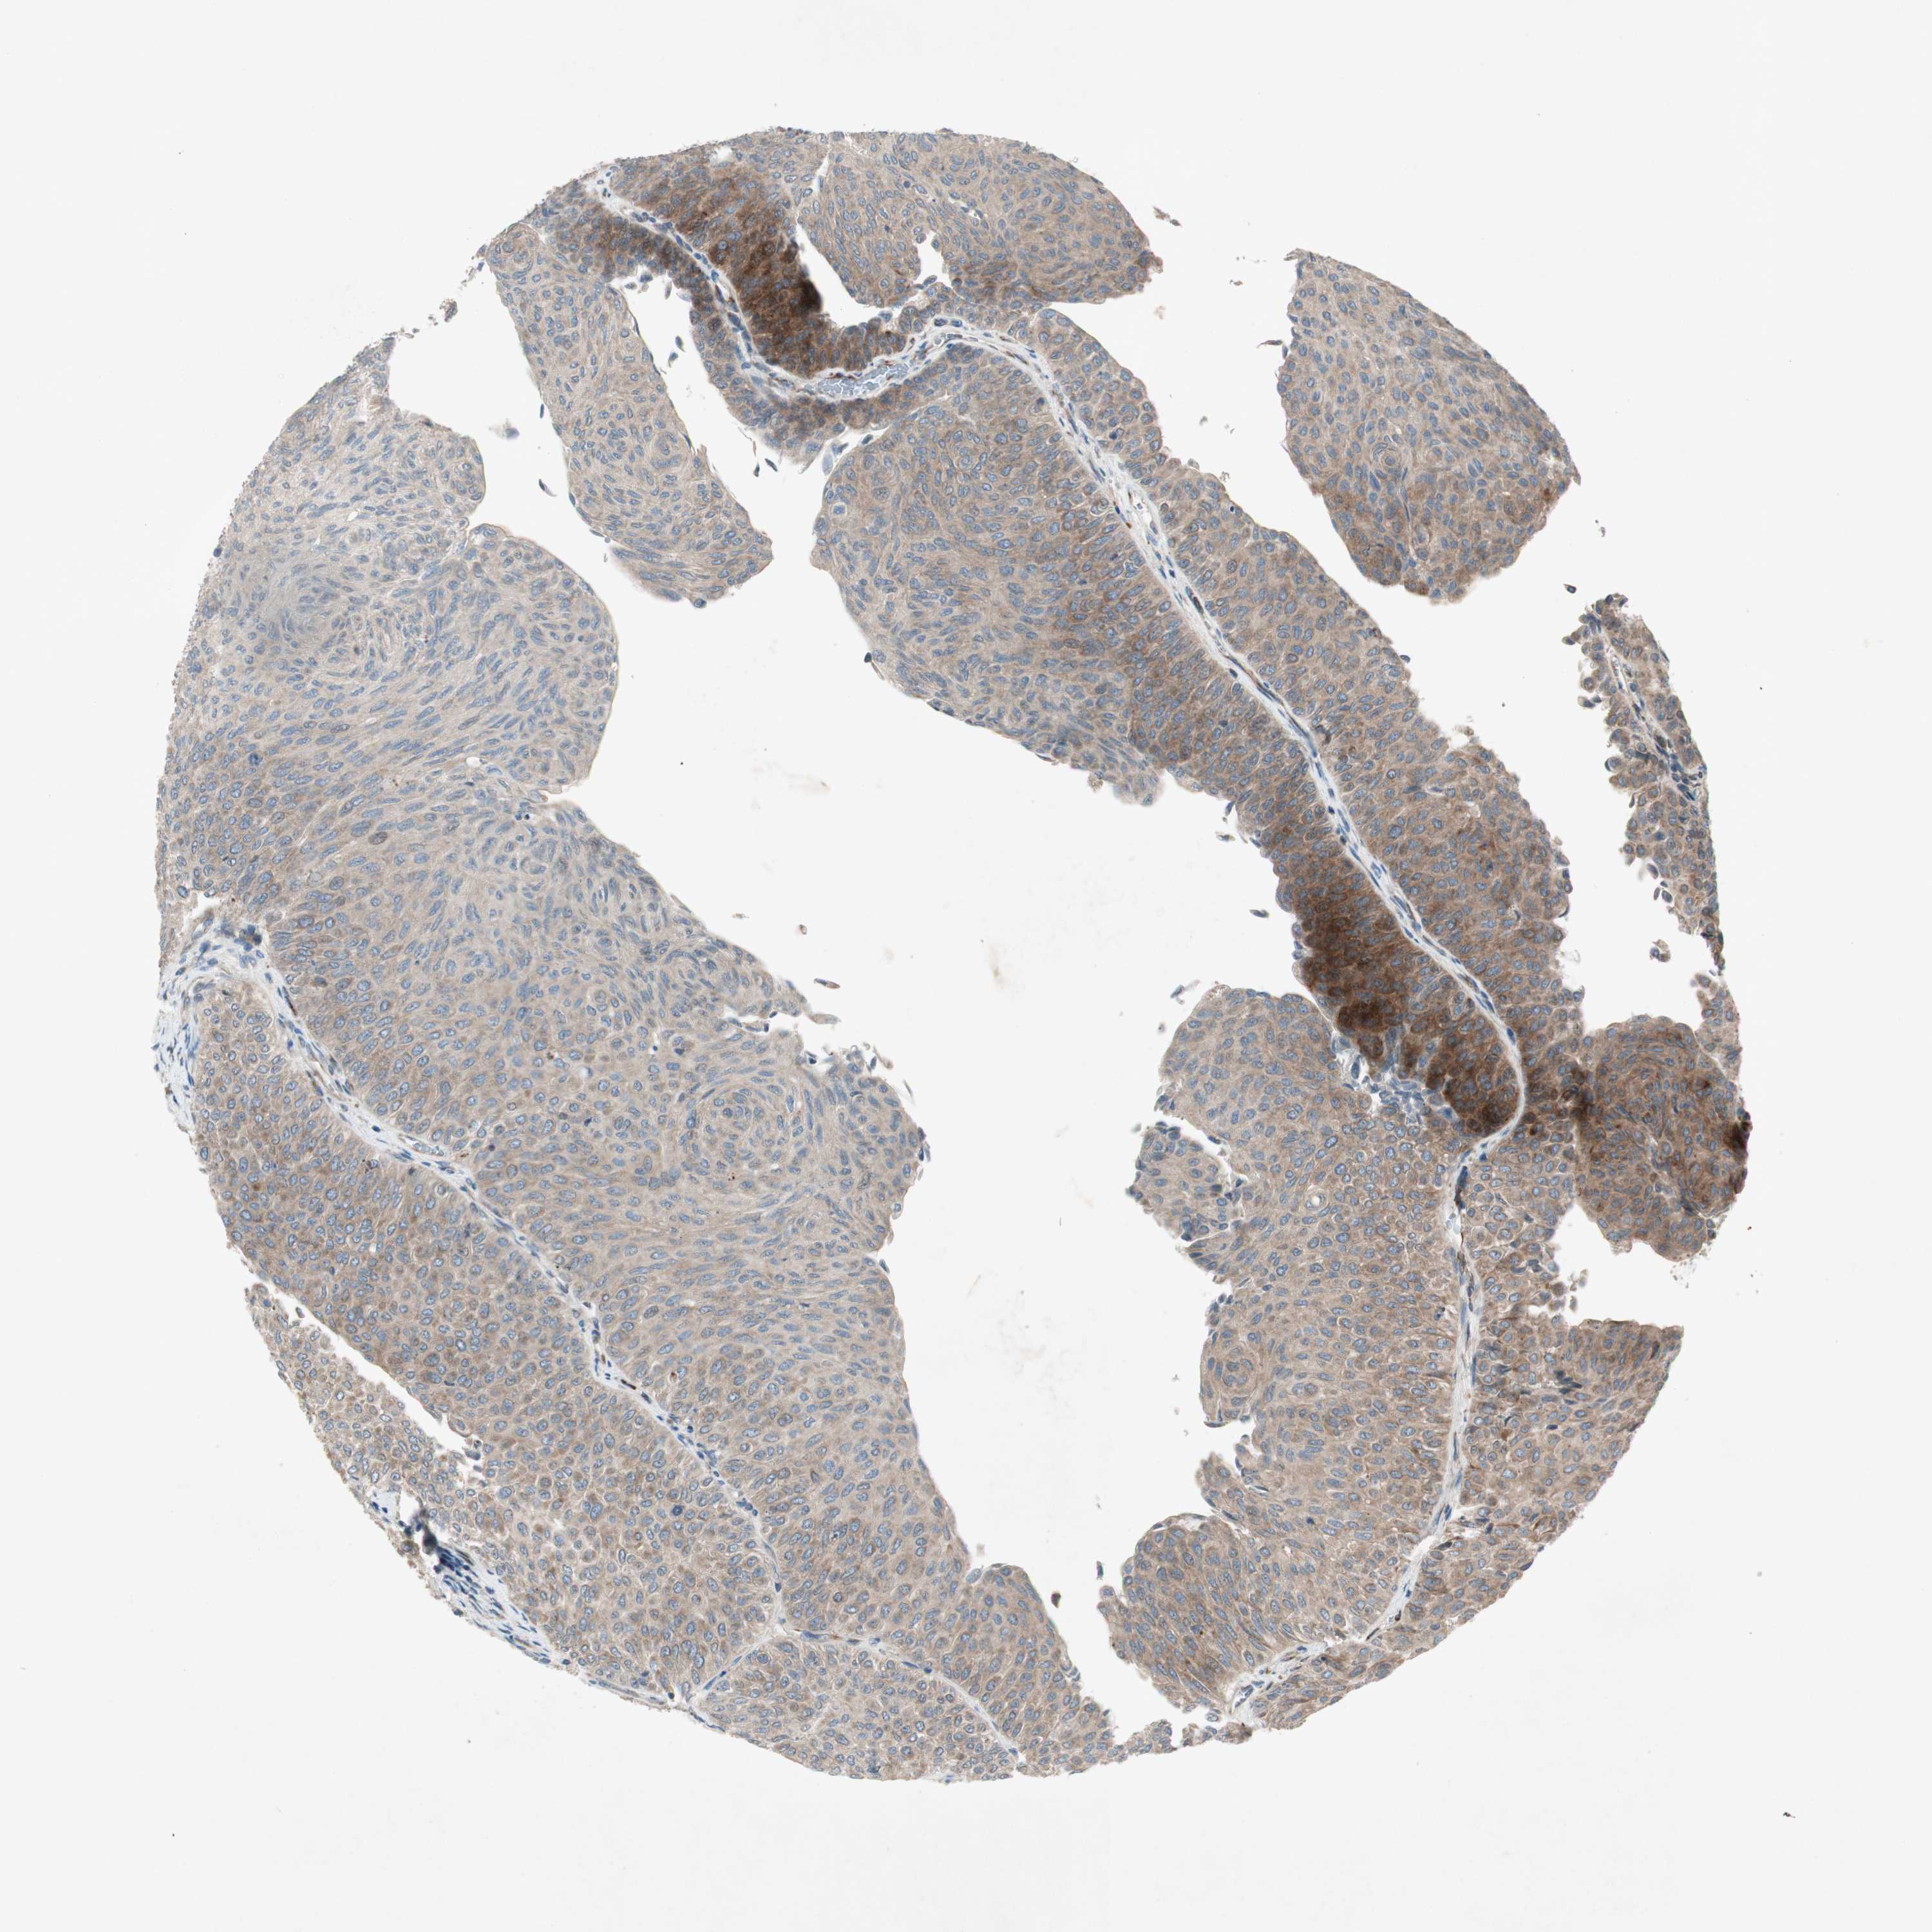

UROTHELIAL CANCER - Protein expressioni

A mouse-over function shows sample information and annotation data. Click on an image to view it in a full screen mode. Samples can be filtered based on level of antibody staining by selecting one or several of the following categories: high, medium, low and not detected. The assay and annotation is described here.

Note that samples used for immunohistochemistry by the Human Protein Atlas do not correspond to samples in the TCGA dataset.

Antibody stainingi

Antibody staining in the annotated cell types in the current human tissue is reported as not detected, low, medium, or high, based on conventional immunohistochemistry profiling in selected tissues. This score is based on the combination of the staining intensity and fraction of stained cells.

Each image is clickable and will lead to virtual microscopy that enables deeper exploration of all samples and also displays staining intensity scores, fraction scores and subcellular localization as well as patient and tissue information for each sample.

Antibody HPA003187

Staining

High

Medium

Low

Not detected

Intensity

Strong

Moderate

Weak

Negative

Quantity

>75%

75%-25%

<25%

None

Location

Nuclear

Cytoplasmic/membranous

Cytoplasmic/membranous,nuclear

Urothelial carcinoma, Low grade

Urothelial carcinoma, High grade